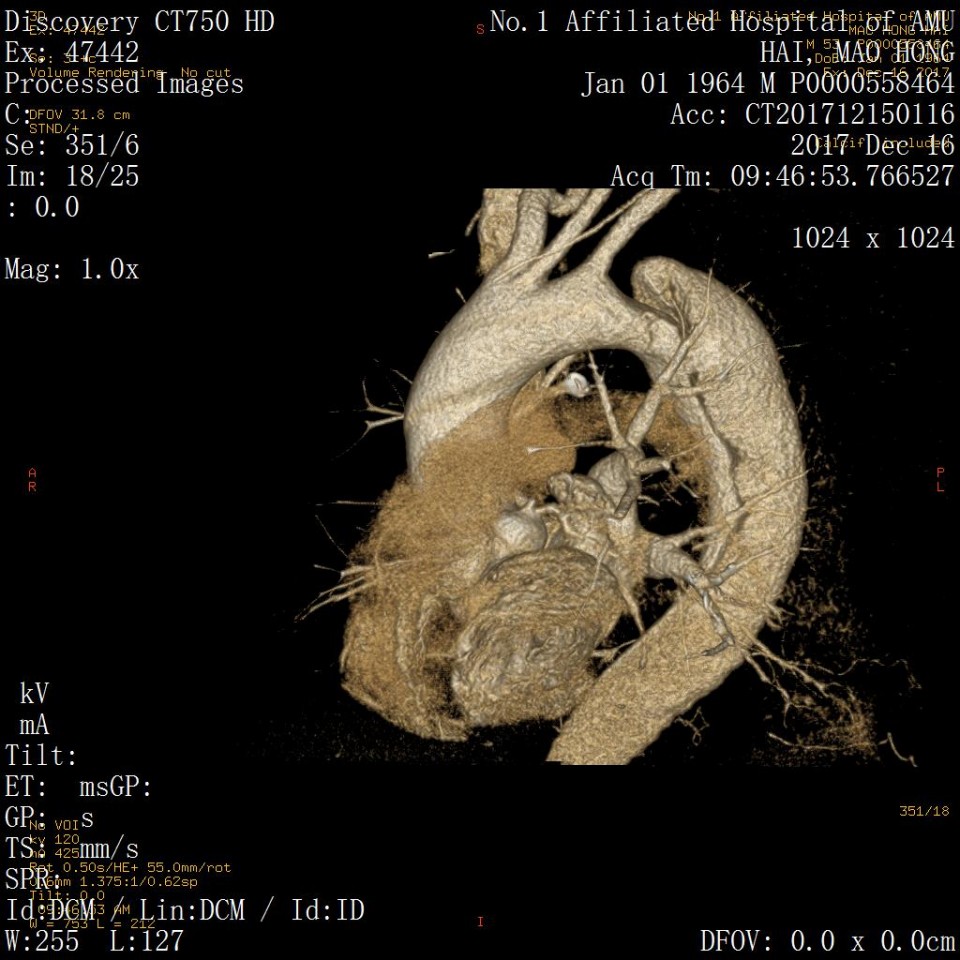

近日,我院血管外科成功应用Castor分支型支架(图1)治疗胸主动脉夹层一例,该病例为我省的首例植入。患者男性,53岁,因“突发胸痛2天”入院,既往有高血压病史。经CTA检查诊断为胸主动脉夹层,破口距离左锁骨下动脉(LSA)36mm,假腔逆撕至左锁LSA(图2、3)。既往一般选用直管型支架,需要部分或全部封闭LSA,但可能增加脑梗和截瘫风险。考虑到患者年龄较轻又是体力劳动者,经科室讨论决定使用Castor一体式分支型覆膜支架,一方面通过增加健康锚定区 (LCCA-LSA距离+LSA直径),进一步降低支架对于血管壁的刺激,从而降低夹层逆撕的风险;另一方面重建LSA保留功能,且不影响LCCA血流。 整个手术过程顺利,最后造影:Castor分支型支架定位精准,无移位;支架近端三重小波段密封性能良好,无内漏,破口被完全封堵,真腔被打开;LSA及LCCA血流通畅,手术圆满成功。病人术后恢复良好(图4、5、6)。